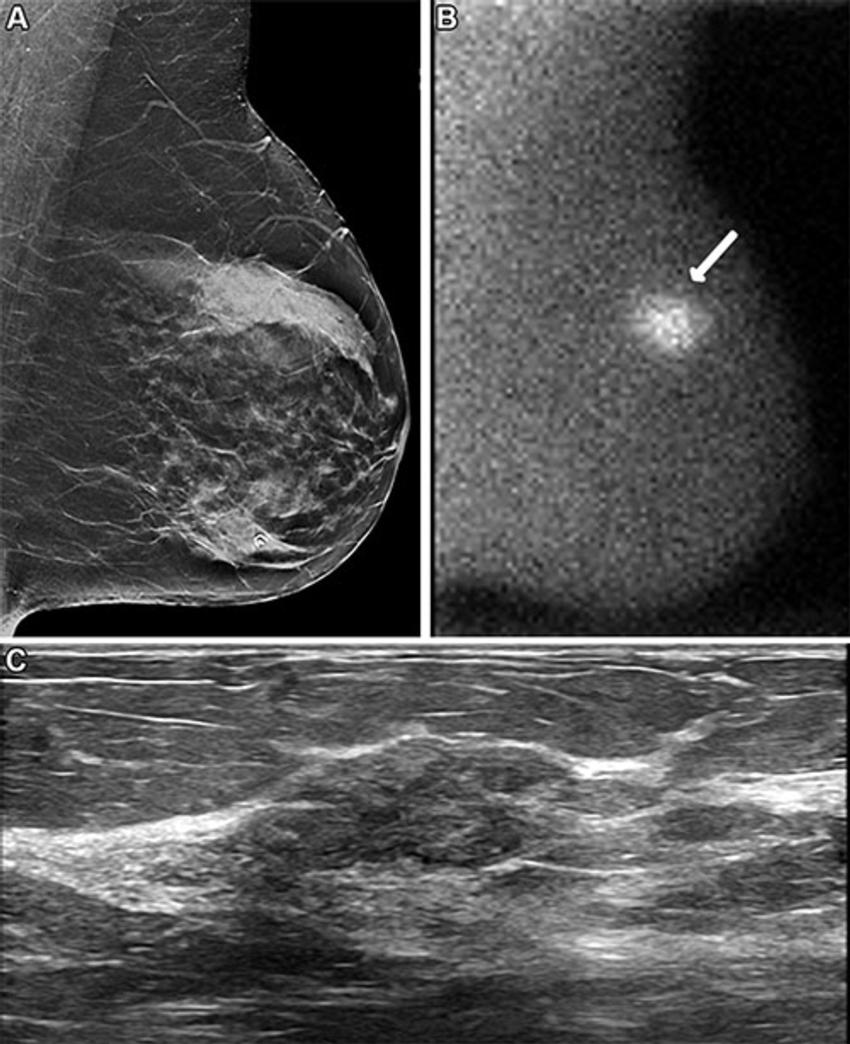

Figure 2. Images in a 62-year-old woman who presented for screening. (A) Image from digital breast tomosynthesis screening (the synthesized two-dimensional mediolateral oblique view of the left breast is shown) at year 1 was interpreted as negative and showing heterogeneously dense breast. (B) Image from molecular breast imaging screening (mediolateral oblique view) at year 1 reveals a 0.9-cm nonmass focal area of uptake in the left breast (arrow). (C) Targeted US scan (transverse image) shows a suspicious mass in the 3-o’clock position of the left breast, 4 cm from the nipple. US-guided core biopsy and lumpectomy revealed a 0.9-cm grade 2 invasive ductal carcinoma, an estrogen receptor–negative, progesterone receptor–negative, human epidermal growth factor receptor 2–negative lesion, with two sentinel nodes negative (N0).